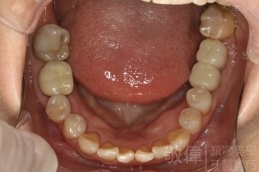

治療前-下顎全口   治療後-下顎全口